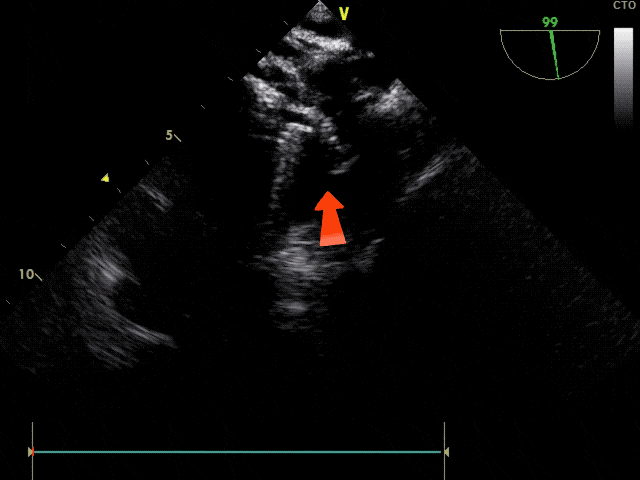

锁定

鞘管及钢缆轻轻前推并固定

释放

确认封堵器锁定形态无误

剪断并撤出成型线

旋拧钢缆,释放封堵器

彩色血流显示封堵成功,无残余分流